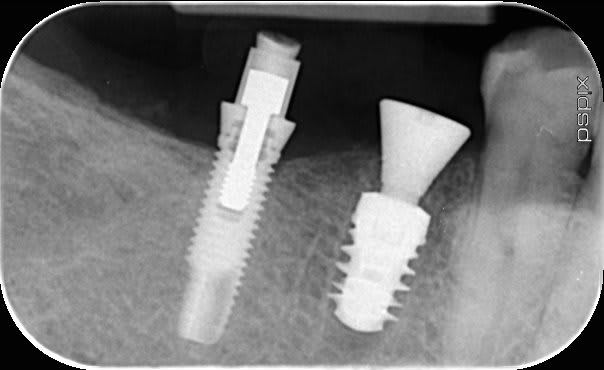

recu ce jour un patient ancien expat en asie je dois faire la prothèse sur ces 2 implants le premier je l ai identifié mais le second(45) non la tête de vis est un carre (jamais vu ca)

je réactualise car je n arrive a rien avec spotimplant des idées sur l implant 46?